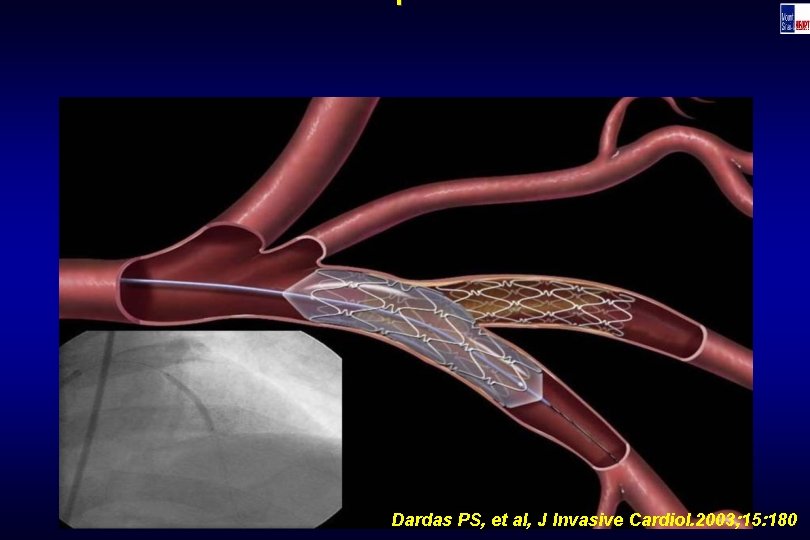

Technique Dardas PS, et al, J Invasive Cardiol. 2003; 15: 180

Technique Dardas PS, et al, J Invasive Cardiol. 2003; 15: 180

Technique Dardas PS, et al, J Invasive Cardiol. 2003; 15: 180

Technique Dardas PS, et al, J Invasive Cardiol. 2003; 15: 180

Technique Dardas PS, et al, J Invasive Cardiol. 2003; 15: 180

Technique Dardas PS, et al, J Invasive Cardiol. 2003; 15: 180